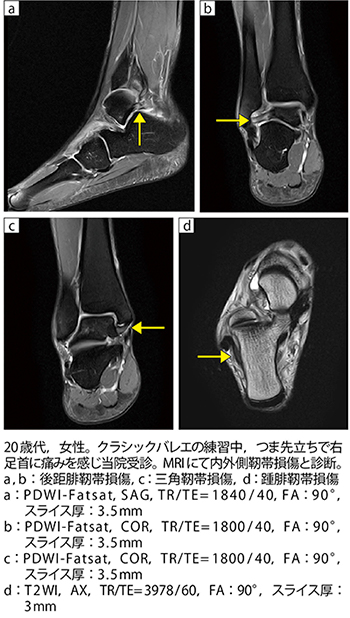

■症例1:内外側靭帯損傷